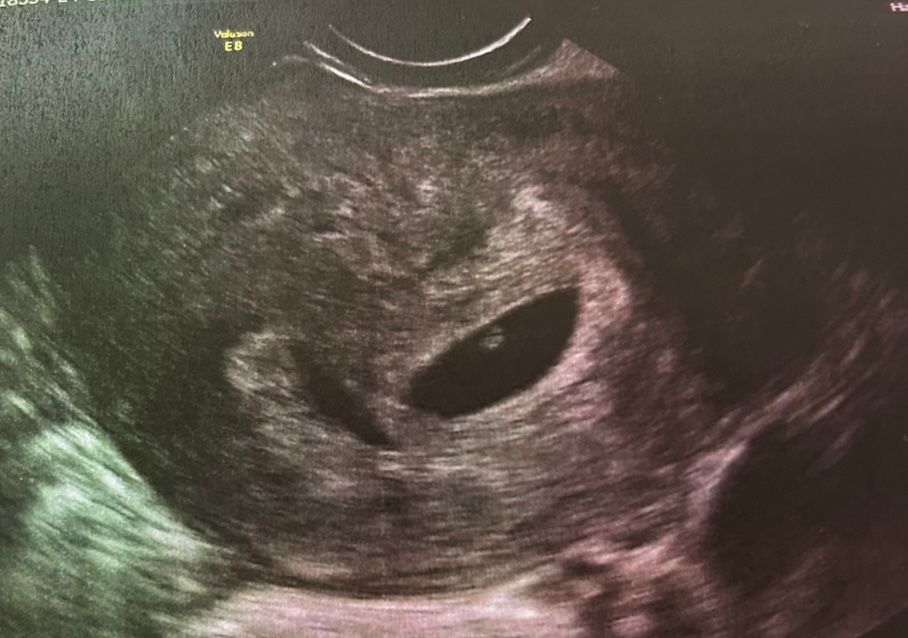

Результаты: УЗИ, КТГ, доплера, скринингаБыла сегодня впервые на узи, оказывается у меня могла бы быть двойня. Один растет хорошо, crl 5 mm, сердце бьется. Второй замер яйцом 4 мм. Доктор сказал ничего делать не надо, но рекомендует сделать НИПТ тест.